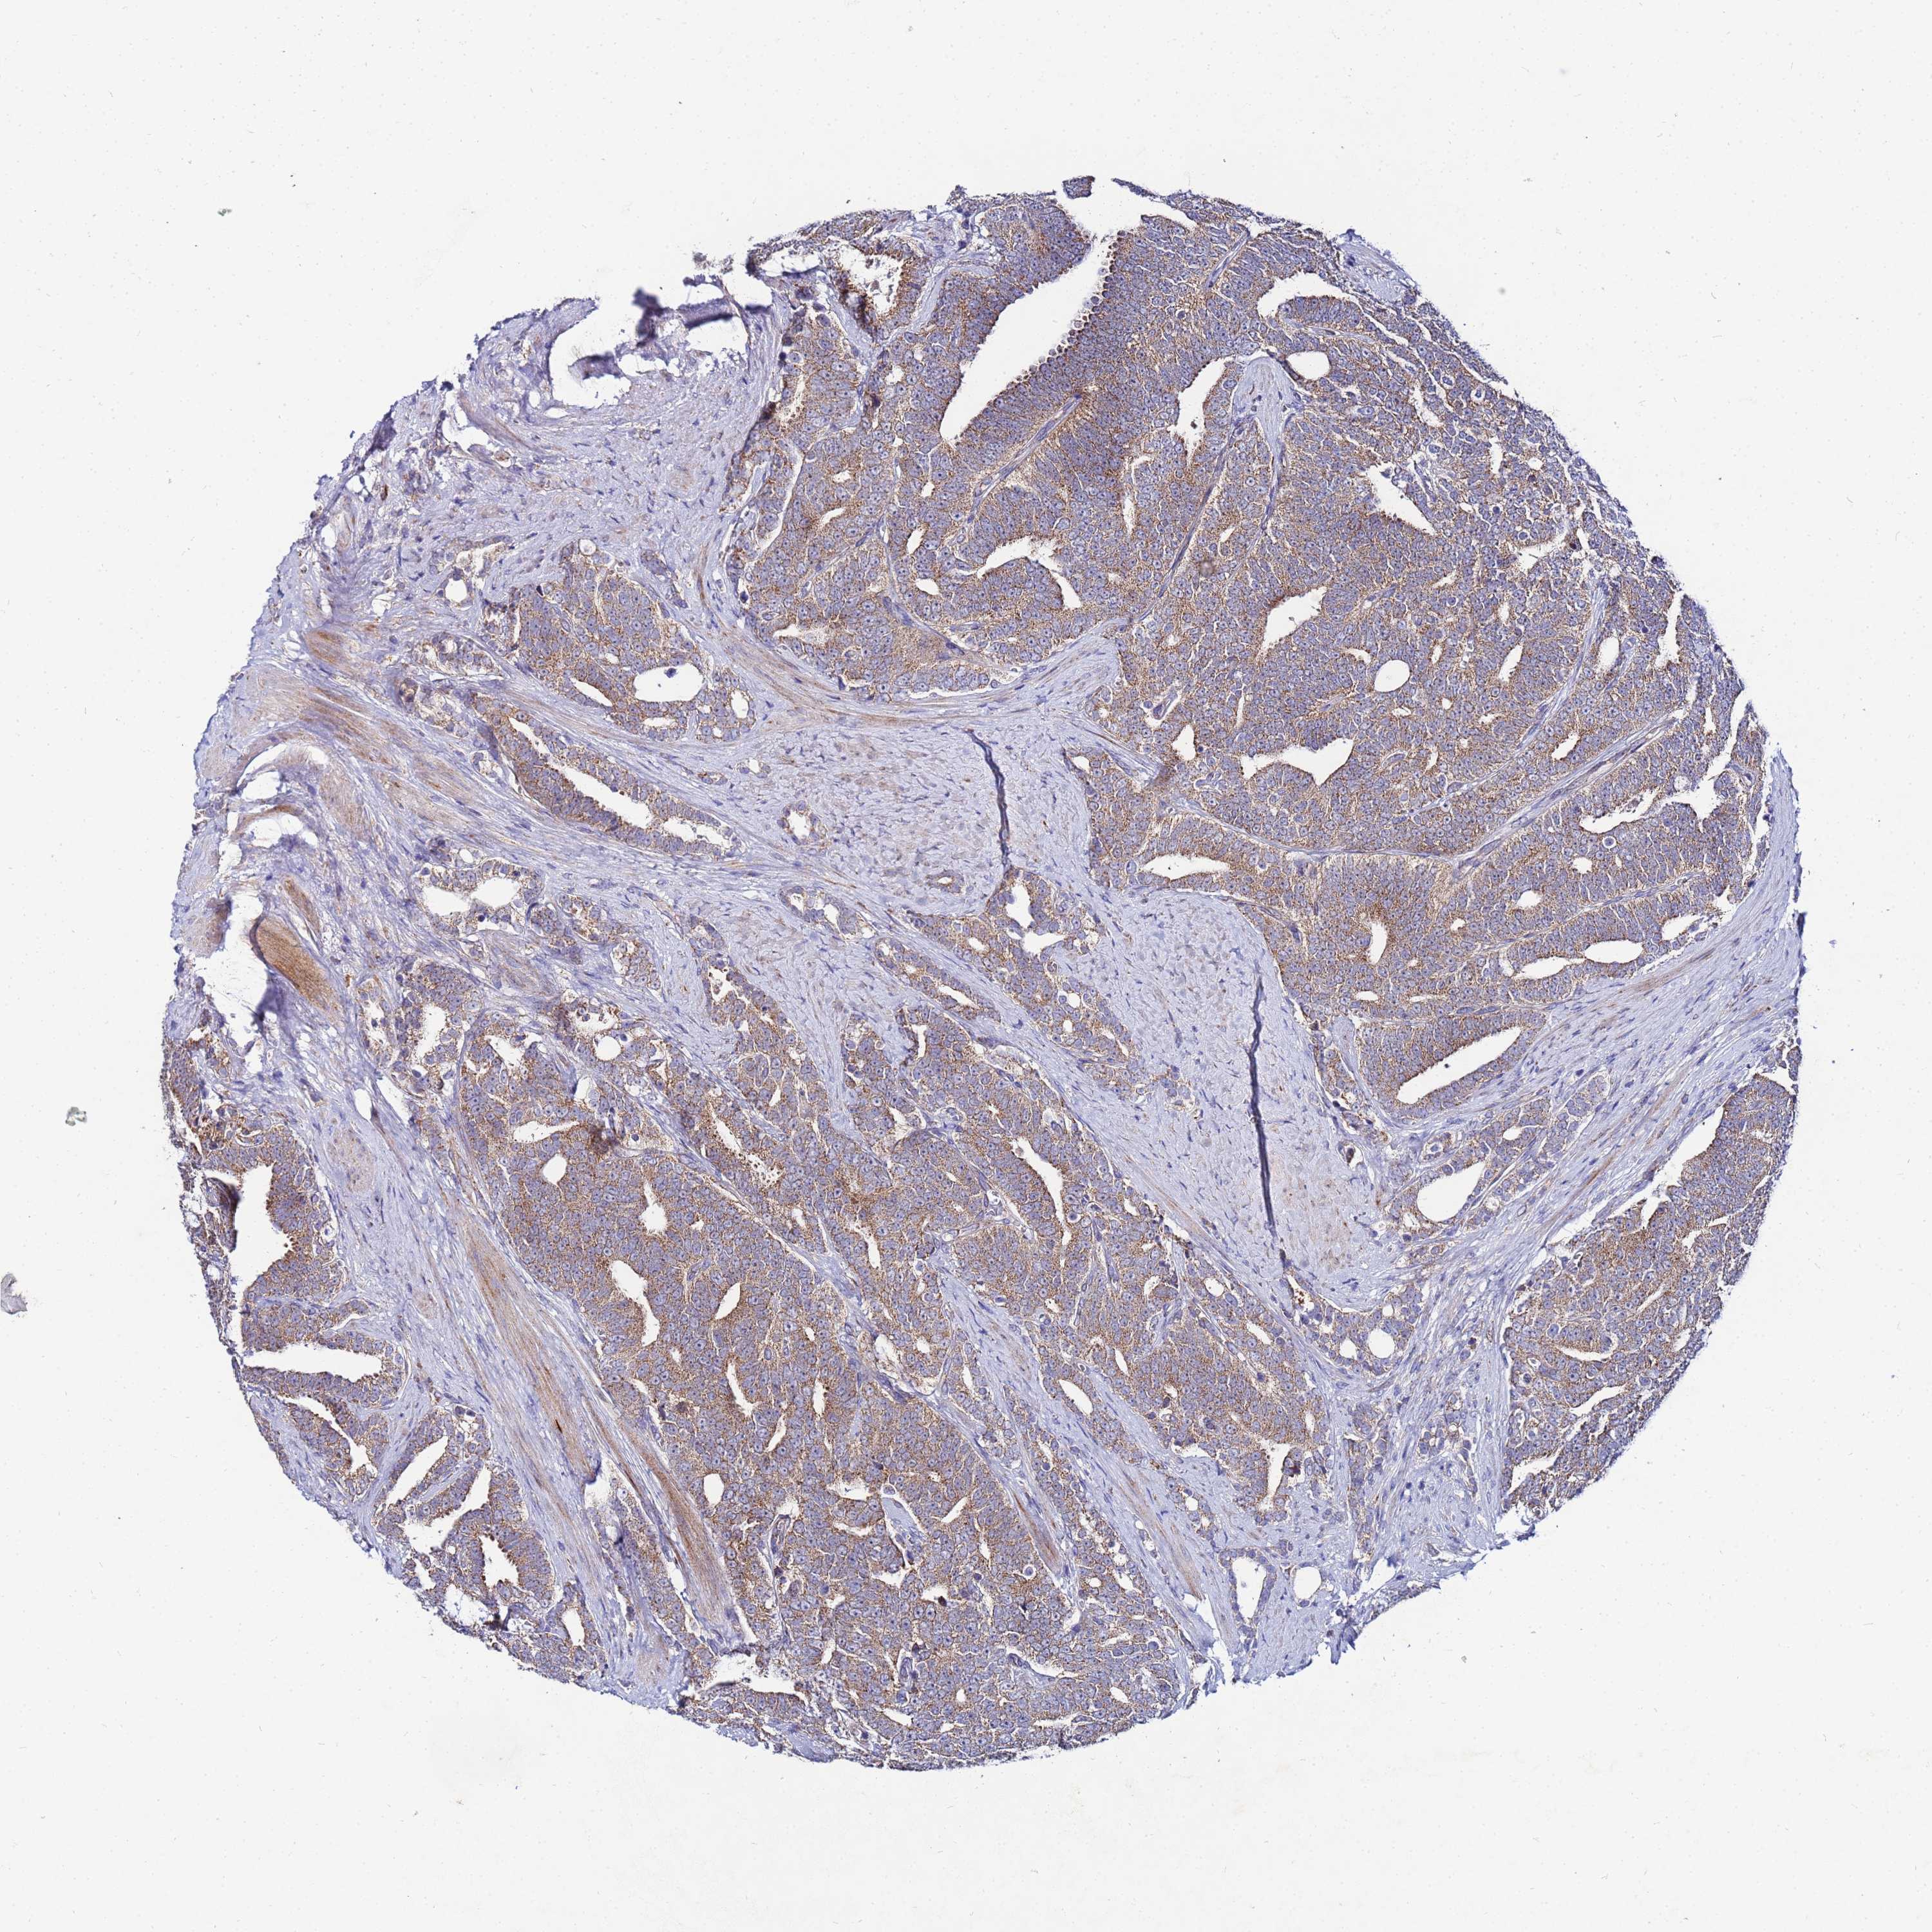

PROSTATE CANCER - Protein expressioni

A mouse-over function shows sample information and annotation data. Click on an image to view it in a full screen mode. Samples can be filtered based on level of antibody staining by selecting one or several of the following categories: high, medium, low and not detected. The assay and annotation is described here.

Antibody stainingi

Antibody staining in the annotated cell types in the current human tissue is reported as not detected, low, medium, or high, based on conventional immunohistochemistry profiling in selected tissues. This score is based on the combination of the staining intensity and fraction of stained cells.

Each image is clickable and will lead to virtual microscopy that enables deeper exploration of all samples and also displays staining intensity scores, fraction scores and subcellular localization as well as patient and tissue information for each sample.

Antibody HPA042145

Antibody HPA044987

Antibody CAB045971

Antibody CAB045972

Staining

High

Medium

Low

Not detected

Intensity

Strong

Moderate

Weak

Negative

Quantity

>75%

75%-25%

<25%

None

Location

Nuclear

Cytoplasmic/membranous

Cytoplasmic/membranous,nuclear

Adenocarcinoma, NOS

Adenocarcinoma, High grade

Adenocarcinoma, Low grade